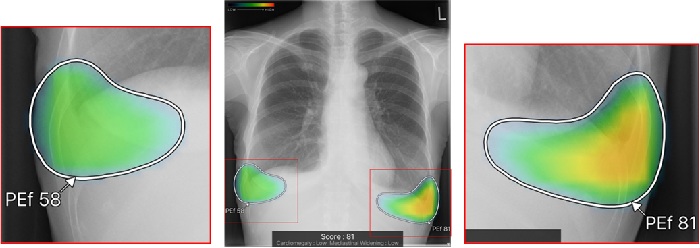

また、異常所見の存在可能性(確信度)を青から赤へのグラデーションで示すヒートマップ表示は、モノクロモニターでは確認しにくいという声を受け、異常所見の疑われる領域の表示方法で、「ヒートマップ表示」「輪郭表示」「ヒートマップと輪郭の併用表示」と3つの表示パターンを選択できるようにした。

従来のバージョンでは、複数の異常所見を検出した場合、検出された異常所見のうち最も確信度が高い所見のスコアのみ表示していたが、新バージョンでは、検出領域に対応する所見名と確信度を示すスコアを個別に表示できるようにした。